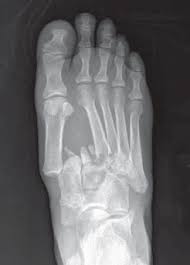

Radiologists must have a thorough understanding of anatomy, mechanisms, and patterns of these injuries to diagnose and help. A lisfranc injury, also known as a lisfranc fracture, happens when bones break or ligaments tear in the region in the middle of the feet. A lisfranc injury occurs when one or more of the metatarsal bones are displaced from the tarsus, which is a cluster of bones at the top of the foot, just below the ankle joint. However, most athletes are able to successfully. Stable lisfranc injuries that do not require surgery may cause an athlete to miss 2 months or more of their season. Lisfranc injuries are a spectrum of injuries to the tarsometatarsal joint complex of the midfoot. Lisfranc injury or midfoot injury that result if bones in the midfoot are broken or ligaments that support the midfoot are torn. • medial edge of 2nd mt base should line up with the medial edge of middle cuneiform. A lisfranc injury or lisfranc sprain is an injury to the ligaments in the middle part of the foot, called the midfoot. Lisfranc injury indicates disruption between. Recovery can be slow and painful. It can occur in one or both feet. Ebraheim's animated educational video describing lisfranc injury.